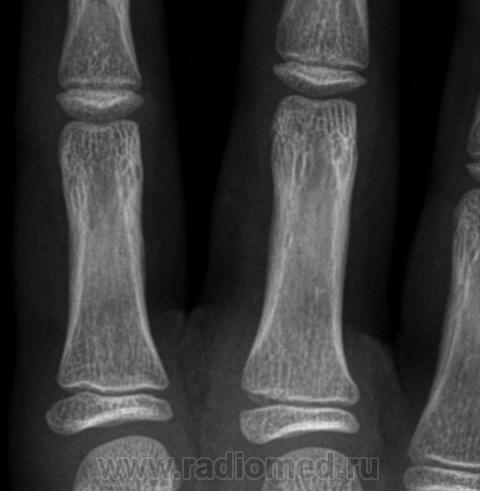

Остеоэпифизеолиз о/ф III пальца.

Спасибо Валентин Львович за обработку изображений, в данном случае остеоэпифизиолиз проксимальной фаланги 3п.. В косой проекции кстати даже четко видно ступеньку.